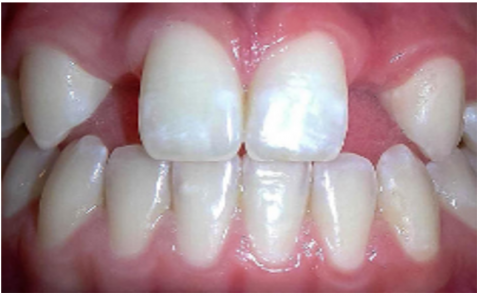

The dataset used in this study consists of 10,573 clinically sourced dental images, including contributions from publicly available repositories such as Kaggle. It provides a comprehensive foundation for training, validating, and testing the dental disease detection system [15]. The images are categorized into five distinct dental conditions: caries (2,382 images), gingivitis (2,349 images), hypodontia (1,251 images), mouth ulcers (2,541 images), and tooth discoloration (2,050 images) (Figure 1).

a

b

c

d

e

Figure 1. Dataset samples. (a) Caries, (b) Gingivitis, (c) Hypodontia, (d) Mouth ulcers, (e) Tooth discoloration